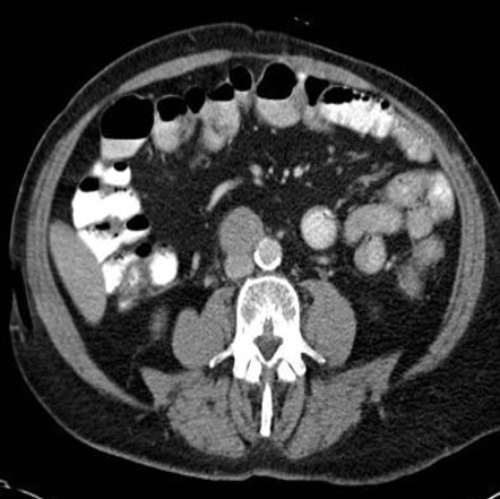

Figure 3. Axial CT showing left para-aortic lymph node from a left sided tumour.

Figure 4. Axial CT showing aortocaval lymph node from a right sided tumour.

Stage two disease has abdominal lymph nodes; 2a nodes <2cm, 2b nodes 2-5cm, 2c at least one node >5cm. Retroperitoneal lymph nodes are the commonest site for metastatic disease and left sided tumours tend to spread to left para-aortic lymph nodes (Figure 3) and right sided tumours to aorto-caval or precaval nodes [3] (Figure 4). It is important to carefully evaluate the relevant area depending on the site of the tumour.